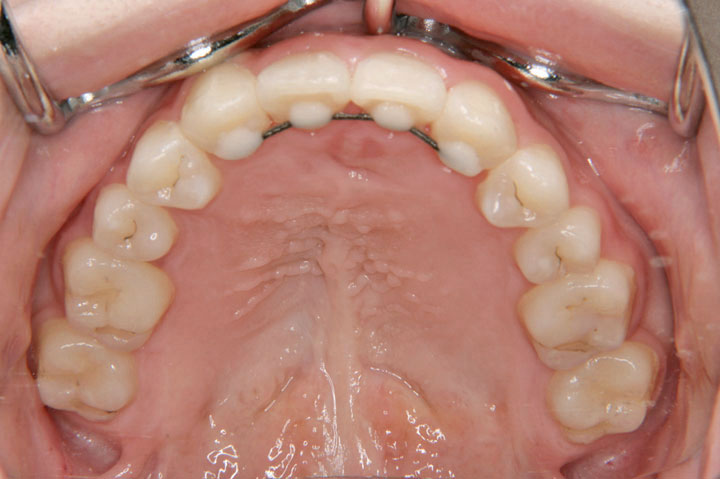

口唇口蓋裂患児のため、関連病院からの紹介で当院を受診されました。小学校4年生の女子です。口蓋裂のため上顎の側方への成長が悪く、拡大床、クォードヘリックスを用い、側方拡大を行いました。その後、永久歯列への交換を待って、エッジワイズ治療を行っております。また、上顎側切歯が両側とも欠損でしたが、大きな違和感もなく配列することができました。